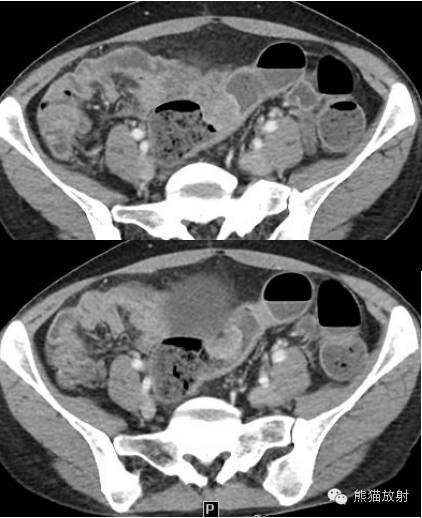

女,19岁,每次来月经时咯血。

CT诊断:结合病史,考虑左下肺子宫内膜异位症(渗出型),建议月经间期复查。

女,33岁,2年余前在月经期时,出现尿频、尿急,伴全程肉眼血尿,呈淡红色,无血块,有时可有尿痛;经期结束后,上述症状消失。

膀胱镜检查:膀胱三角区及各壁粘膜可见充血炎性改变,三角区后方可见一范围约1.5×2cm的粘膜隆起,局部可见紫蓝色的粘膜下瘀斑,于该处取病理2;

活检病理示:(膀胱)送检少许组织被覆尿路上皮,呈轻度慢性炎,间质中查见少数散在的腺体,结合临床和免疫表型,符合子宫内膜异位;免疫组化:ER 、PR 、CD10-、CK34βE12±、CK7±。